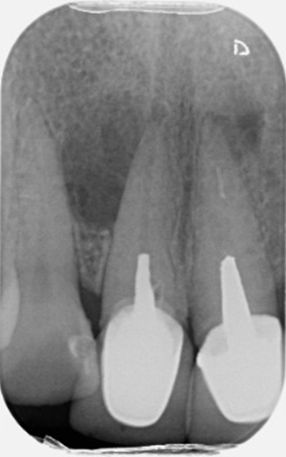

Open/Immature apex management and internal whitening

Pre-op